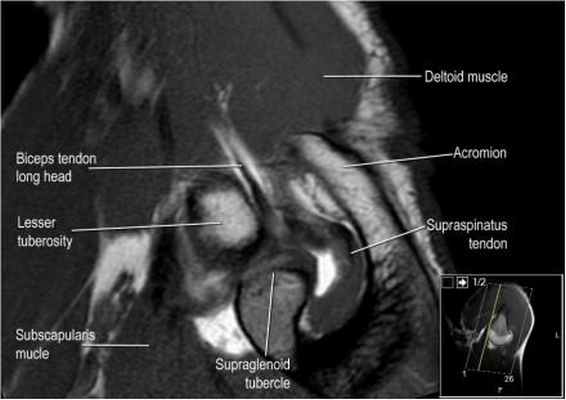

Ось сухожилия надостной мышцы

Подвергаясь тендинопатие и повреждению, сухожилие надостной мышцы является важнейшей частью манжеты вращателей. Повреждения сухожилия надостной мышцы лучше видны в косой корональной плоскости и в положении отведения и поворота плеча кнаружи (ABER - abduction external rotation). В большинстве случаев ось сухожилия надостной мышцы (головки стрелок) отклонена кпереди от оси мышцы (желтая стрелка). При планировании косой корональной проекции лучше ориентироватьия на ось сухожилия надостной мышцы.